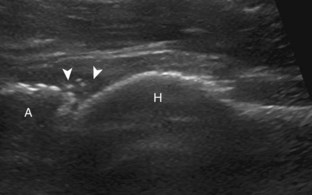

Thigh Evaluation: Posterior

Structures of interest in the posterior thigh include the semimembranosus, the semitendinosus, the biceps femoris, and the sciatic nerve. Ultrasound evaluation can begin in the transverse plane at the level of the mid-thigh, or more proximally at the horizontal gluteal crease or ischial tuberosity. At the level of the mid-posterior thigh (Fig. 6-20A), three distinct muscles can be identified medial to lateral, which are the semimembranosus, semitendinosus, and biceps femoris muscles (see Fig. 6-20B). The short head of the biceps femoris can be identified deep to the long head at the femoral cortex at the level of the mid-femur. When the transducer is moved in the transverse plane distally toward the knee, the semitendinosus becomes a thin tendon and moves directly superficial to the semimembranosus muscle (see Fig. 6-20B to D). This is an additional finding that aids the identification of the posterior thigh muscles. In the mid-thigh, the honeycomb appearance of the sciatic nerve can be identified between the biceps femoris muscle and the semitendinosus muscle (see Fig. 6-20B).